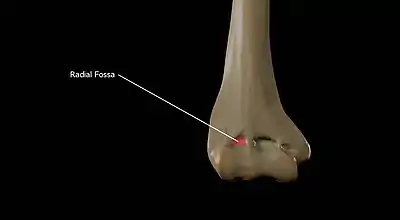

Above the front part of the capitulum is a slight depression, the radial fossa, which receives the anterior border of the head of the radius, when the forearm is flexed.

Radial Fossa of the Humerus